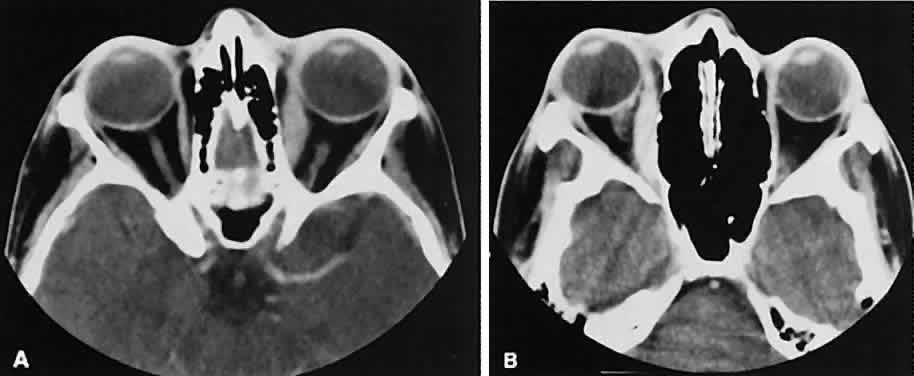

By altering window setting and level of attenuation on the console, subtle differences in tissuecomposition or bone changes can be appreciated.Window setting refers to the amount of the pixel sampling used by the computer to determine image contrast. Level refers to the scale of density used by the computer to create the image. Both the window setting and level of attenuation are extremely important, for example, when evaluating lesions in the fossa of the lacrimal gland, when the surrounding bone must be examined carefully for either pressure thinning or tumor erosion.

An appreciation for the various pathologic processes that affect the orbit is facilitated by an understanding of the normal orbital anatomy (Fig. 1). The orbit is a pyramid-shaped bony structure bounded inferiorly by the maxillary sinus, medially by the ethmoidal sinus, and superiorly by the frontal sinus. The sphenoidal sinus is situated posteriorly along the medial orbital wall and has a common wall with the optic canal. The lacrimal gland lies within its fossa located in the superior temporal aspect of the orbit and can be seen on both axial and coronal views.

The extraocular muscles (EOMs), with the exception of the inferior oblique, originate from the anulus of Zinn in the orbital apex. The inferior oblique takes its origin from the frontal process of the maxilla and is seen occasionally on CT imaging. The superior oblique, after originating from the anulus, courses along the superior nasal orbital wall just above the medial rectus muscle before passing through the trochlea. The rectus muscles conveniently form a muscle cone, which is sometimes helpful in terms of differential diagnosis. Before thinner axial slices and multiplanar imaging were available, an enlarged inferior rectus muscle often was imaged as an apical mass, especially if dysthy-roid optic neuropathy was present. The importance of imaging from two different planes cannot be overemphasized in this situation.

The superior ophthalmic vein (SOV) is an important vascular structure to recognize. It begins in the superior nasal quadrant near the trochlea before coursing posteriorly and laterally beneath the superior rectus muscle, exiting the orbit through the superior orbital fissure. Drainage is into the cavernous sinus. Asymmetric enlargement, especially in the presence of an ipsilateral cavernous sinus enlargement, suggests a vascular anomaly, which may require selective carotid angiography for further definition. Enlargement of one or multiple EOMs in this setting is likely. The SOV also may be enlarged as a result of any process impeding drainage from the orbital apex, such as dysthyroid orbitopathy or metastatic disease.